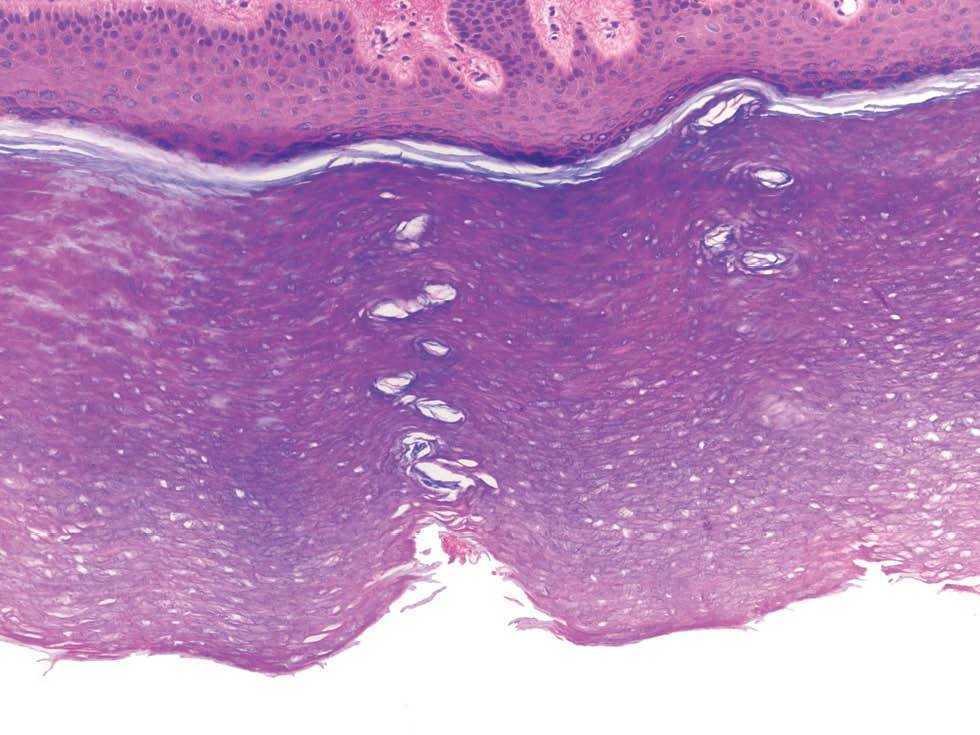

Una mujer de 20 años, con antecedentes personales de alergia a gramíneas y rinoconjuntivitis alérgica, consultó por lesiones blanquecinas y asintomáticas en las palmas de ambas manos aparecidas 8 meses antes, tras haber estado en una piscina. Duraban escasos minutos y desaparecían espontáneamente. Las lesiones reaparecían de forma continua desde entonces, al entrar en contacto con agua fría o caliente. En la exploración física presentaba, en el centro de ambas palmas, una ligera hiperqueratosis. Tras sumergir las manos en agua durante 5 min mostró una coloración blanquecina de la piel, que adquirió un aspecto macerado de las palmas, junto a pápulas pequeñas de color blanco (figs. 1 y 2). Con la impresión clínica de acroqueratodermia siríngea acuagénica se le realizó biopsia de una de las lesiones, apreciándose discreta hiperqueratosis ortoqueratósica, acantosis difusa y una ligera dilatación del acrosiringio (fig. 3). En la dermis papilar se observaron discretos infiltrados linfocitarios de localización preferentemente perivascular.

Fig. 3.--Imagen histológica donde se observan dos acrosiríngeos levemente dilatados. (Hematoxilina-eosina, x20.)